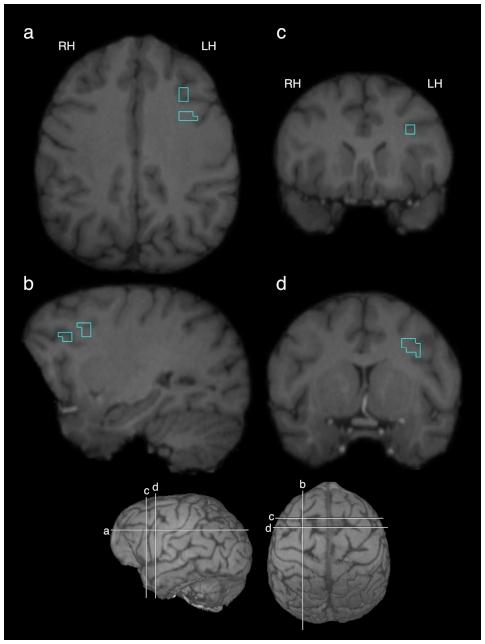

The evolutionary origin of human language and its neurobiological foundations has long been the object of intense scientific debate. Although a number of theories have been proposed, one particularly contentious model suggests that human language evolved from a manual gestural communication system in a common ape-human ancestor. Consistent with a gestural origins theory are data indicating that chimpanzees intentionally and referentially communicate via manual gestures, and the production of manual gestures, in conjunction with vocalizations, activates the chimpanzee Broca's area homologue--a region in the human brain that is critical for the planning and execution of language. However, it is not known if this activity observed in the chimpanzee Broca's area is the result of the chimpanzees producing manual communicative gestures, communicative sounds, or both. This information is critical for evaluating the theory that human language evolved from a strictly manual gestural system. To this end, we used positron emission tomography (PET) to examine the neural metabolic activity in the chimpanzee brain. We collected PET data in 4 subjects, all of whom produced manual communicative gestures. However, 2 of these subjects also produced so-called attention-getting vocalizations directed towards a human experimenter. Interestingly, only the two subjects that produced these attention-getting sounds showed greater mean metabolic activity in the Broca's area homologue as compared to a baseline scan. The two subjects that did not produce attention-getting sounds did not. These data contradict an exclusive "gestural origins" theory for they suggest that it is vocal signaling that selectively activates the Broca's area homologue in chimpanzees. In other words, the activity observed in the Broca's area homologue reflects the production of vocal signals by the chimpanzees, suggesting that this critical human language region was involved in vocal signaling in the common ancestor of both modern humans and chimpanzees.